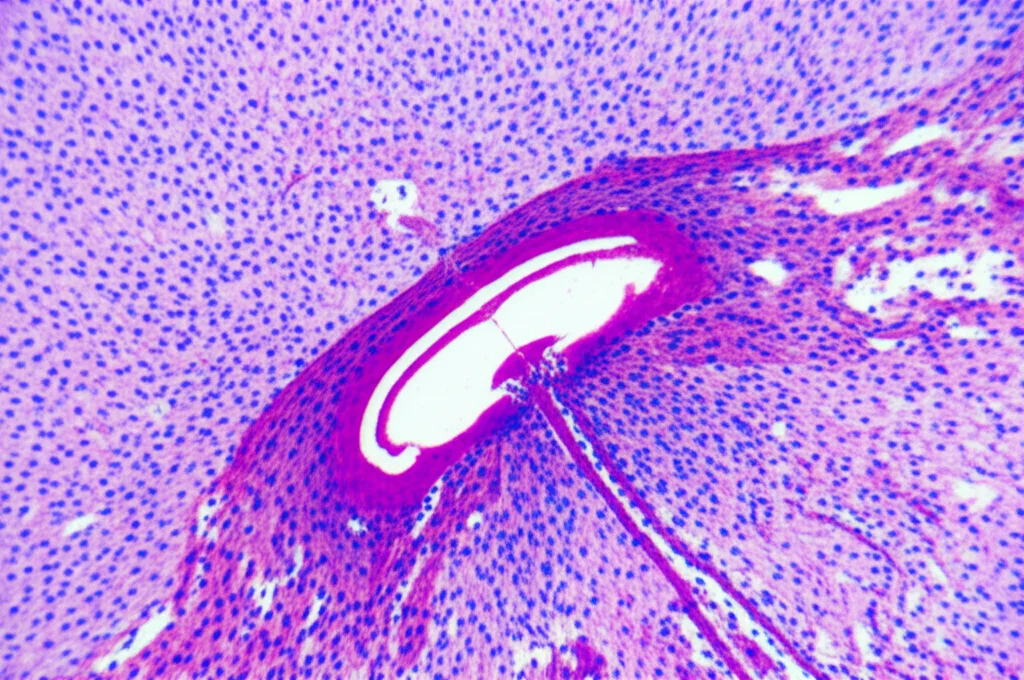

La prima scoperta interessante è stata che, nei topi sottoposti a CUMS, i livelli di LINC00641 nell’ippocampo (un’area del cervello cruciale per umore e memoria) erano significativamente più bassi rispetto ai topi di controllo. Non solo: questi topi mostravano i classici segni depressivi (meno interesse per l’acqua zuccherata, più tempo immobili nei test) e avevano livelli ridotti di serotonina, noradrenalina e dopamina. Inoltre, osservando i loro neuroni ippocampali al microscopio, abbiamo notato segni di sofferenza e un aumento della morte cellulare (apoptosi).